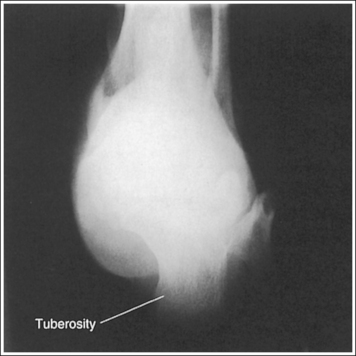

The talocalcaneal joint is demonstrated as an open space, and the calcaneal tuberosity is demonstrated without distortion.

• The talocalcaneal joint space is demonstrated as an open space, and the calcaneal tuberosity appears without distortion, when the correct central ray angulation and foot position are used. For a patient who has foot mobility, place the foot in a neutral-vertical position and direct a 40-degree central ray angulation toward the plantar foot surface (Figure 6-35). This positioning places the central ray parallel with the talocalcaneal joint space and perpendicular to the calcaneal tuberosity (Figure 6-36).

• Compensating for plantar-flexed or dorsiflexed foot. When the patient's foot is dorsiflexed beyond a 90-degree position with the lower leg or is plantar-flexed, the central ray needs to be adjusted to maintain its accurate position with the calcaneal joint space and tuberosity. If the patient's foot is dorsiflexed beyond the vertical position and a 40-degree angulation is used, the calcaneal joint spaces would be obscured and the tuberosity elongated (Figure 6-37; see Image 23). In this situation the central ray angulation should be decreased to maintain accurate central ray alignment. If the patient's foot is plantar-flexed and a 40-degree central ray angulation is used, the calcaneal joint space is obscured and the tuberosity foreshortened (see Image 24 and Figure 6-38). In this situation the central ray angulation should be increased to maintain accurate central ray alignment. The angulation required for each of these situations can be estimated by locating the base of the fifth metatarsal and the distal point of the fibula. The fifth metatarsal base is palpable on the lateral foot surface approximately halfway between the ball of the foot and the heel. Once these structures are located, angle the central ray parallel with an imaginary line drawn between them. When the axial calcaneal projection is taken with the foot in plantar flexion and the central ray is angled as just discussed to demonstrate the talocalcaneal joint space, the calcaneal tuberosity will be elongated because of the acute angle created between the central ray and IR (see Image 25).

The proximal calcaneal tuberosity is at the center of the exposure field. The calcaneal tuberosity and the talocalcaneal joint space are included within the collimated field.

• Centering the central ray to the midline of the foot at the level of the fifth metatarsal base places the proximal tuberosity in the center of the exposure field.

The talocalcaneal joint space is obscured, and the calcaneal tuberosity is elongated. The foot was dorsiflexed beyond the vertical position, and a 40-degree central ray angulation was used.

Plantar-flex the foot to a vertical position and use a 40-degree angulation. If the patient cannot plantar-flex the foot, decrease the degree of central ray angulation, aligning the central ray with the fifth metatarsal base and the distal point of the fibula.

The talocalcaneal joint space is obscured, and the calcaneal tuberosity is foreshortened. The foot was in plantar flexion, and the standard 40-degree central ray angulation was used.

If patient condition allows, dorsiflex the foot to a vertical, neutral position. If the patient cannot dorsiflex the foot, increase the central ray angulation, aligning the central ray with the fifth metatarsal base and the distal point of the fibula. Because of the acute angle that will be set up between the central ray and IR with this method, the calcaneal tuberosity will be elongated (see Image 23).

The talocalcaneal joint space is shown as an open space and the calcaneal tuberosity demonstrates elongation. The foot was in plantar flexion, and the central ray was angled so that it was aligned with an imaginary line that connects the fifth metatarsal tuberosity and the distal point of the fibula. The fourth and fifth metatarsals are demonstrated on the lateral aspect of the foot. The ankle was externally rotated, and/or the foot was everted.

Elongation is not preventable if the patient's foot cannot be dorsiflexed because of the acute angle created between the central ray and IR. Internally rotate the leg until the ankle is in an AP projection, and/or bring the foot to a neutral position without eversion.